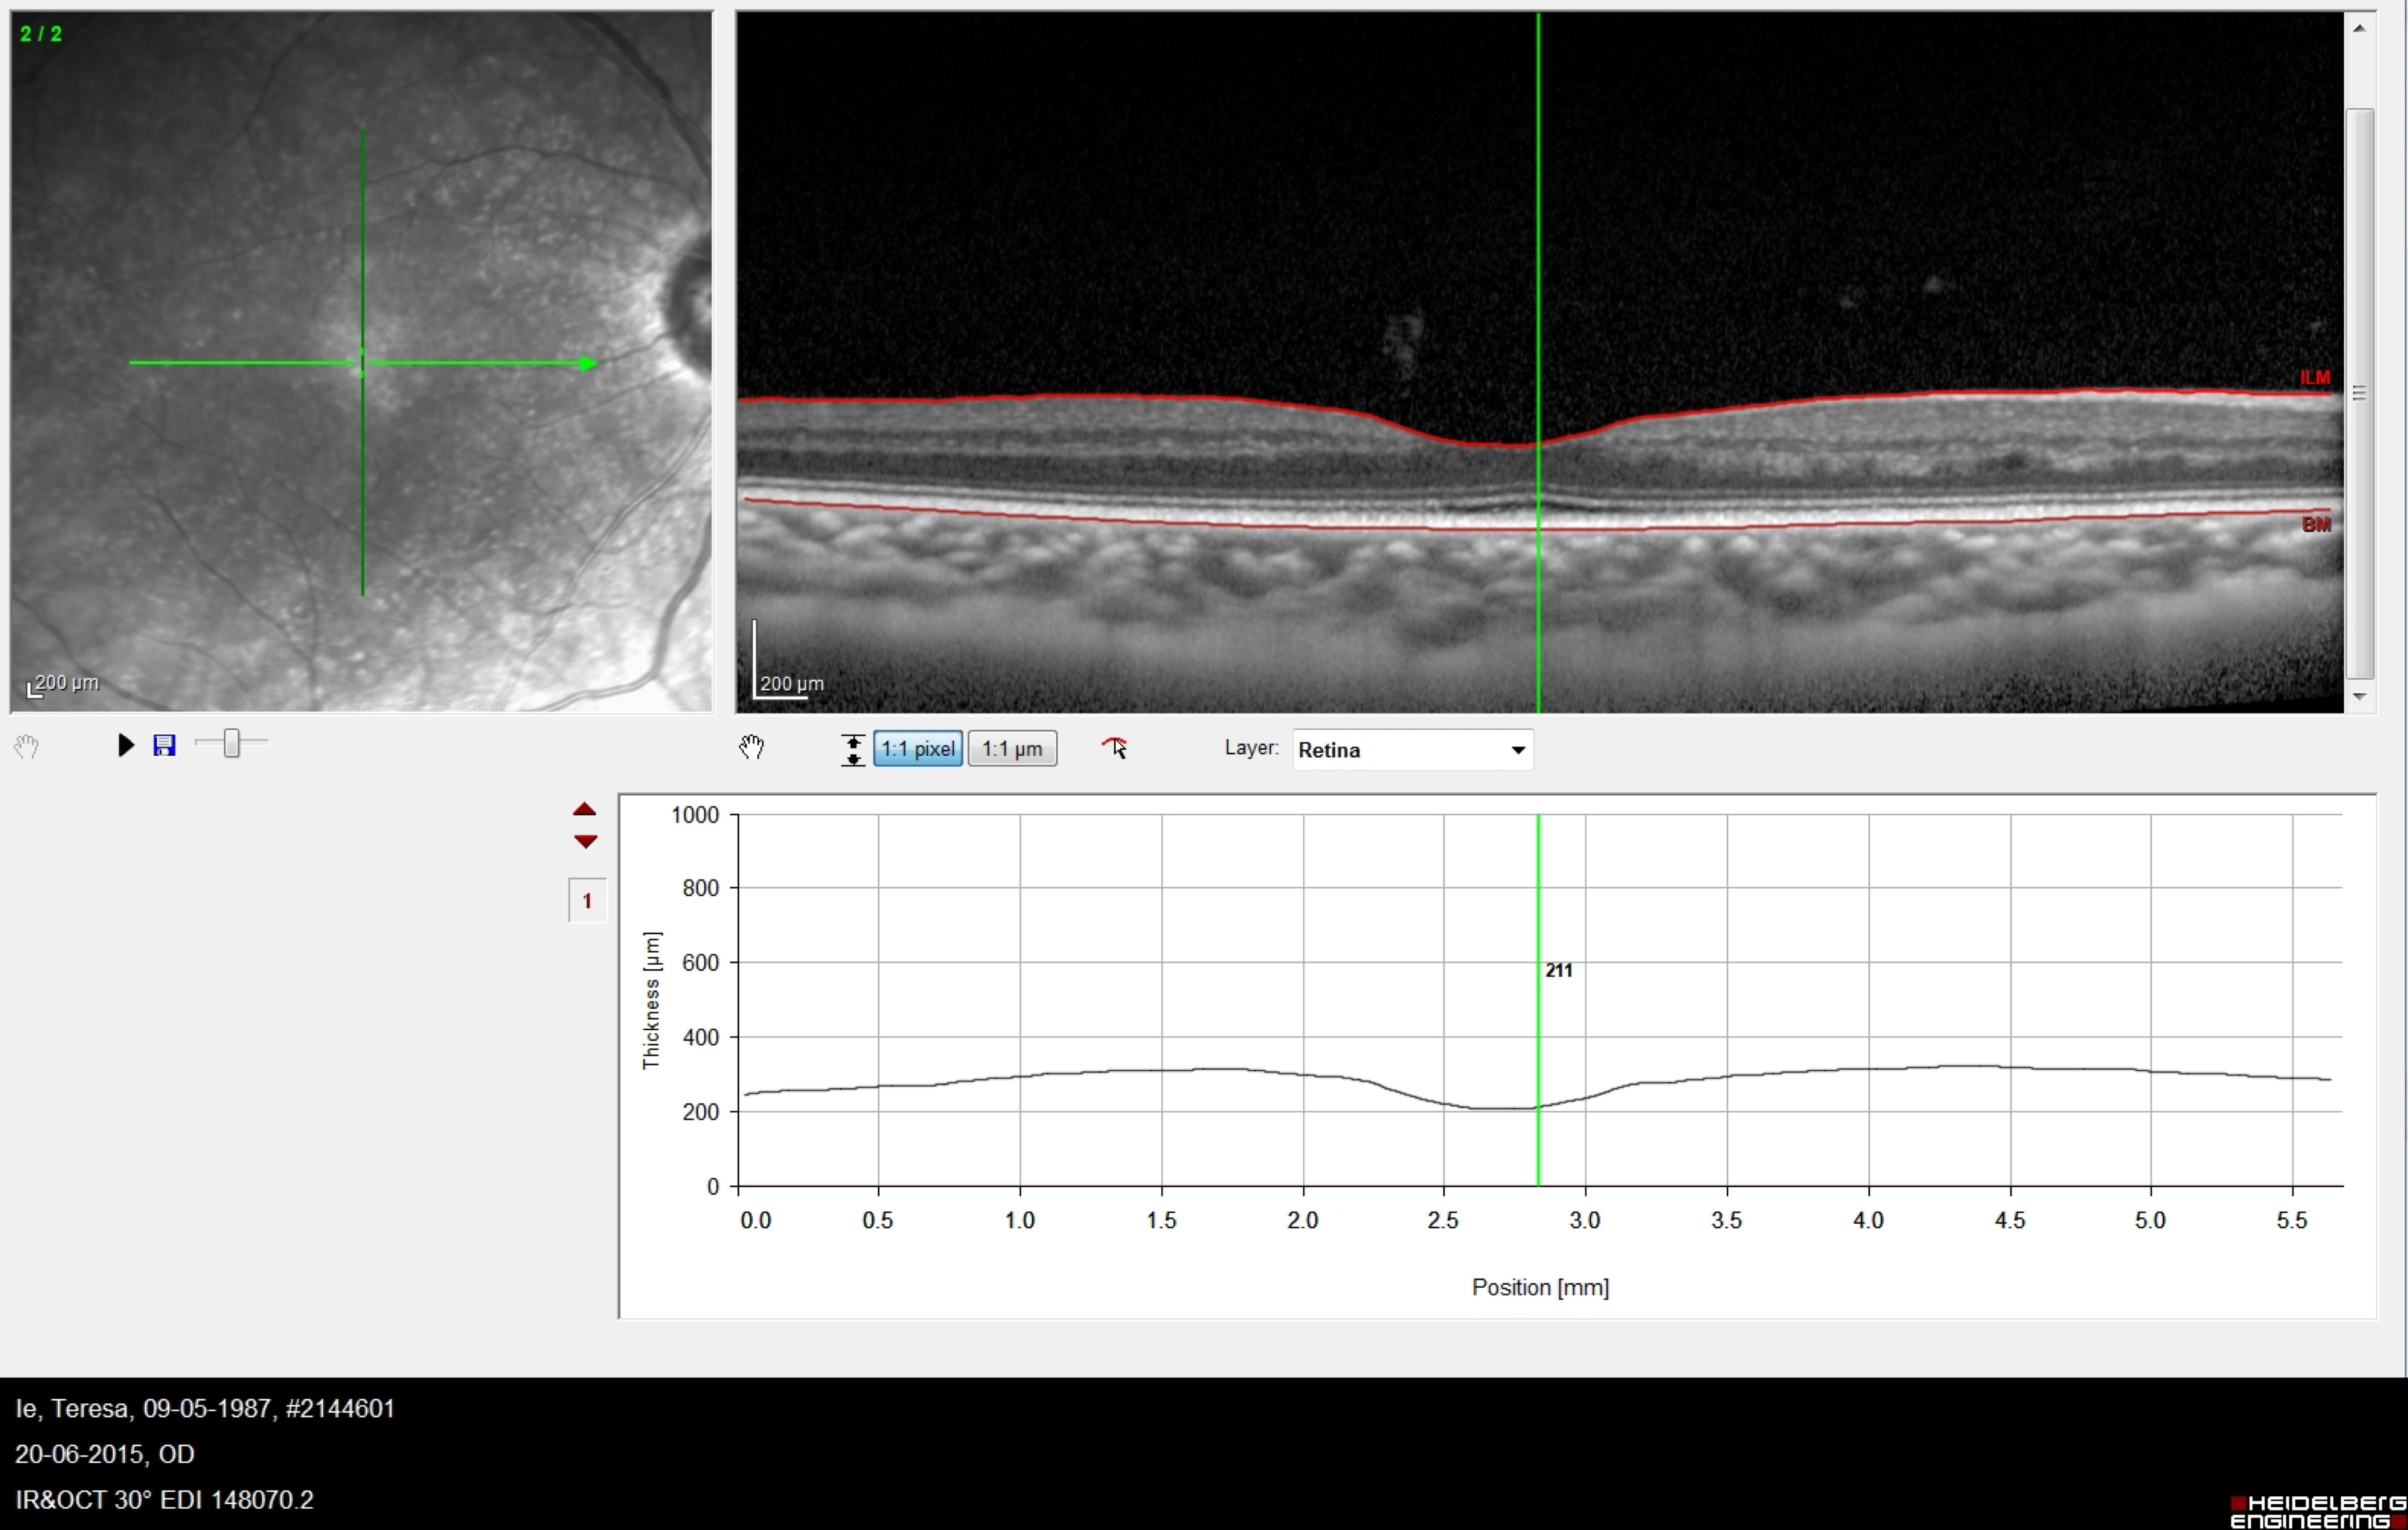

Introdução: A hemodiálise (HD), técnica substitutiva da função renal utilizada em doentes com doença renal crónica terminal (DRCT) está associada a alterações hemodinâmicas bem descritas. O estudo da resposta de tecidos altamente vascularizados como a retina e coroideia a estas alterações hemodinâmicas pode permitir melhorar o conhecimento da fisiologia da circulação ocular. O objectivo deste estudo foi avaliar as alterações, antes e após uma sessão de HD, na espessura da coroideia (espessura da coroideia) nas localizações subfoveal (SF), a 1000 μm nasal (N) e temporal (T) ao centro da fóvea bem como a espessura macular central (EMC) utilizando tomografia de coerência óptica de domínio espectral em modo enhanced-depth imaging (EDI SD-OCT). Materiais e Métodos: estudo prospectivo com 31 olhos de 17 doentes (9 mulheres) com DRCT sob HD crónica. Foram adquiridas imagens de EDI SD-OCT maculares uma hora antes e uma hora após a HD. A espessura da coroideia foi medida manualmente pelo mesmo operador e a EMC determinada automaticamente. Consideramos significância estatística p<0.05. Resultados: A espessura da coroideia nas localizações SF, N e T aumentou de 249.45±12.1 para 266.35±12.2μm (p=0.005), de 221.90±12.8 para 248.10±13.1μm (p<0.005) e de 242.23±11.7 para 271.29±26.2μm (p=0.21), respectivamente. A EMC não alterou significativamente com a HD (de 214.81±6.11 para 214.81±5.8μm, p=1.0). Conclusão: A espessura da coroideia aumentou com a HD em doentes com DRCT. A autorregulação vascular da coroideia e o shifiting de fluido e moléculas entre o sangue e interstício da coroideia podem estar envolvidos na alteração da espessura da coroideia com a HD.